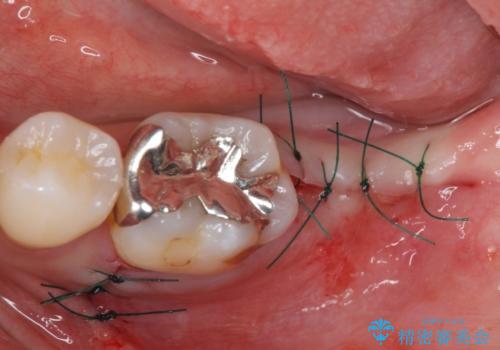

治療期間を短縮することが可能となった、ストローマン社のSLActiveというインプラントを使用し、抜歯からクラウンが装着されるまで6ヶ月という短期間で終えることができました。

咬み心地はもちろん、清掃性もご自分の歯とほとんど変わらない状態となり、患者様には大変満足していただきました。